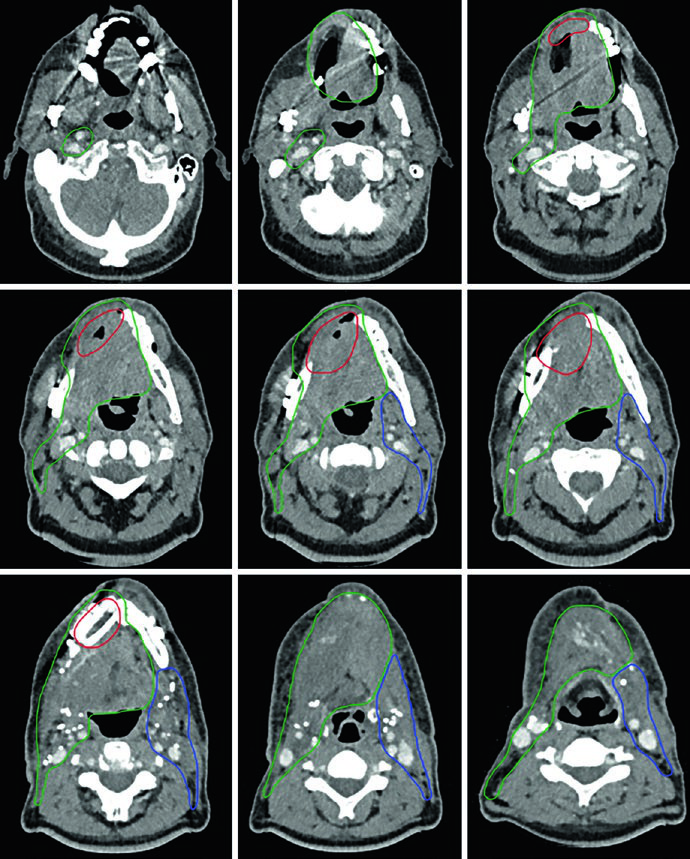

Caso Clínico: Encía T4aN1 con Invasión Ósea

La Figura 6.4 muestra un CEC de encía, T4aN1, con invasión ósea, post-resección con mandibulectomía marginal y vaciamiento cervical izquierdo. El CTV66 (rojo) cubre la región de invasión ósea. El CTV60 (verde) incluye todo el lecho operatorio y los niveles I a IV ipsilaterales.

El CTV54 (azul) abarca los niveles I a IV contralaterales. La decisión de incluir el cuello contralateral se basó en la enfermedad ganglionar positiva (N1) y el estadio T4 — ambos factores que elevan el riesgo de compromiso contralateral. En tumores de encía bien lateralizados con estadificación más favorable, esta cobertura podría omitirse.

Caso Clínico: Piso de Boca T4aN2b

La Figura 6.6 demuestra un CEC de piso de boca, T4aN2b, con invasión mandibular, post-hemimandibulectomía derecha y vaciamiento cervical bilateral. El CTV66 (rojo) abarca el área de extensa invasión ósea. El CTV60 (verde) incluye todo el lecho operatorio y los niveles I a V en el lado ipsilateral.

El espacio retroestiloideo ipsilateral se incluye en el CTV60 como área de alto riesgo para metástasis ganglionar, especialmente con compromiso del nivel II. El CTV60 también se extiende para incluir todo el complejo del piso de boca. El CTV54 (azul) incluye los niveles I a IV contralaterales.

Este caso demuestra cómo la invasión mandibular extensa exige una delineación agresiva de la región de alto riesgo, mientras que la enfermedad ganglionar bilateral justifica cobertura cervical amplia. En la práctica, el tratamiento del piso de boca frecuentemente requiere técnicas de IMRT con planificación cuidadosa para limitar la dosis en mandíbula remanente, glándulas salivares y vía aérea.